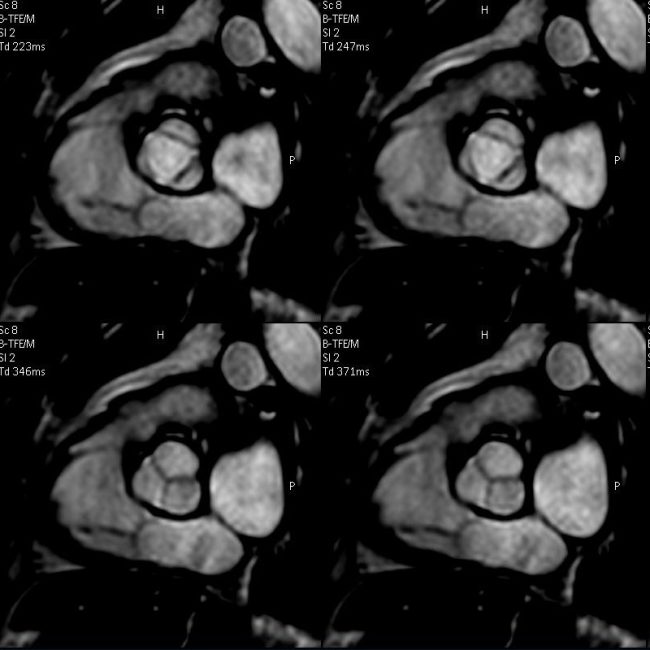

Aortenklappe (oben) geöffnet, (unten) geschlossen